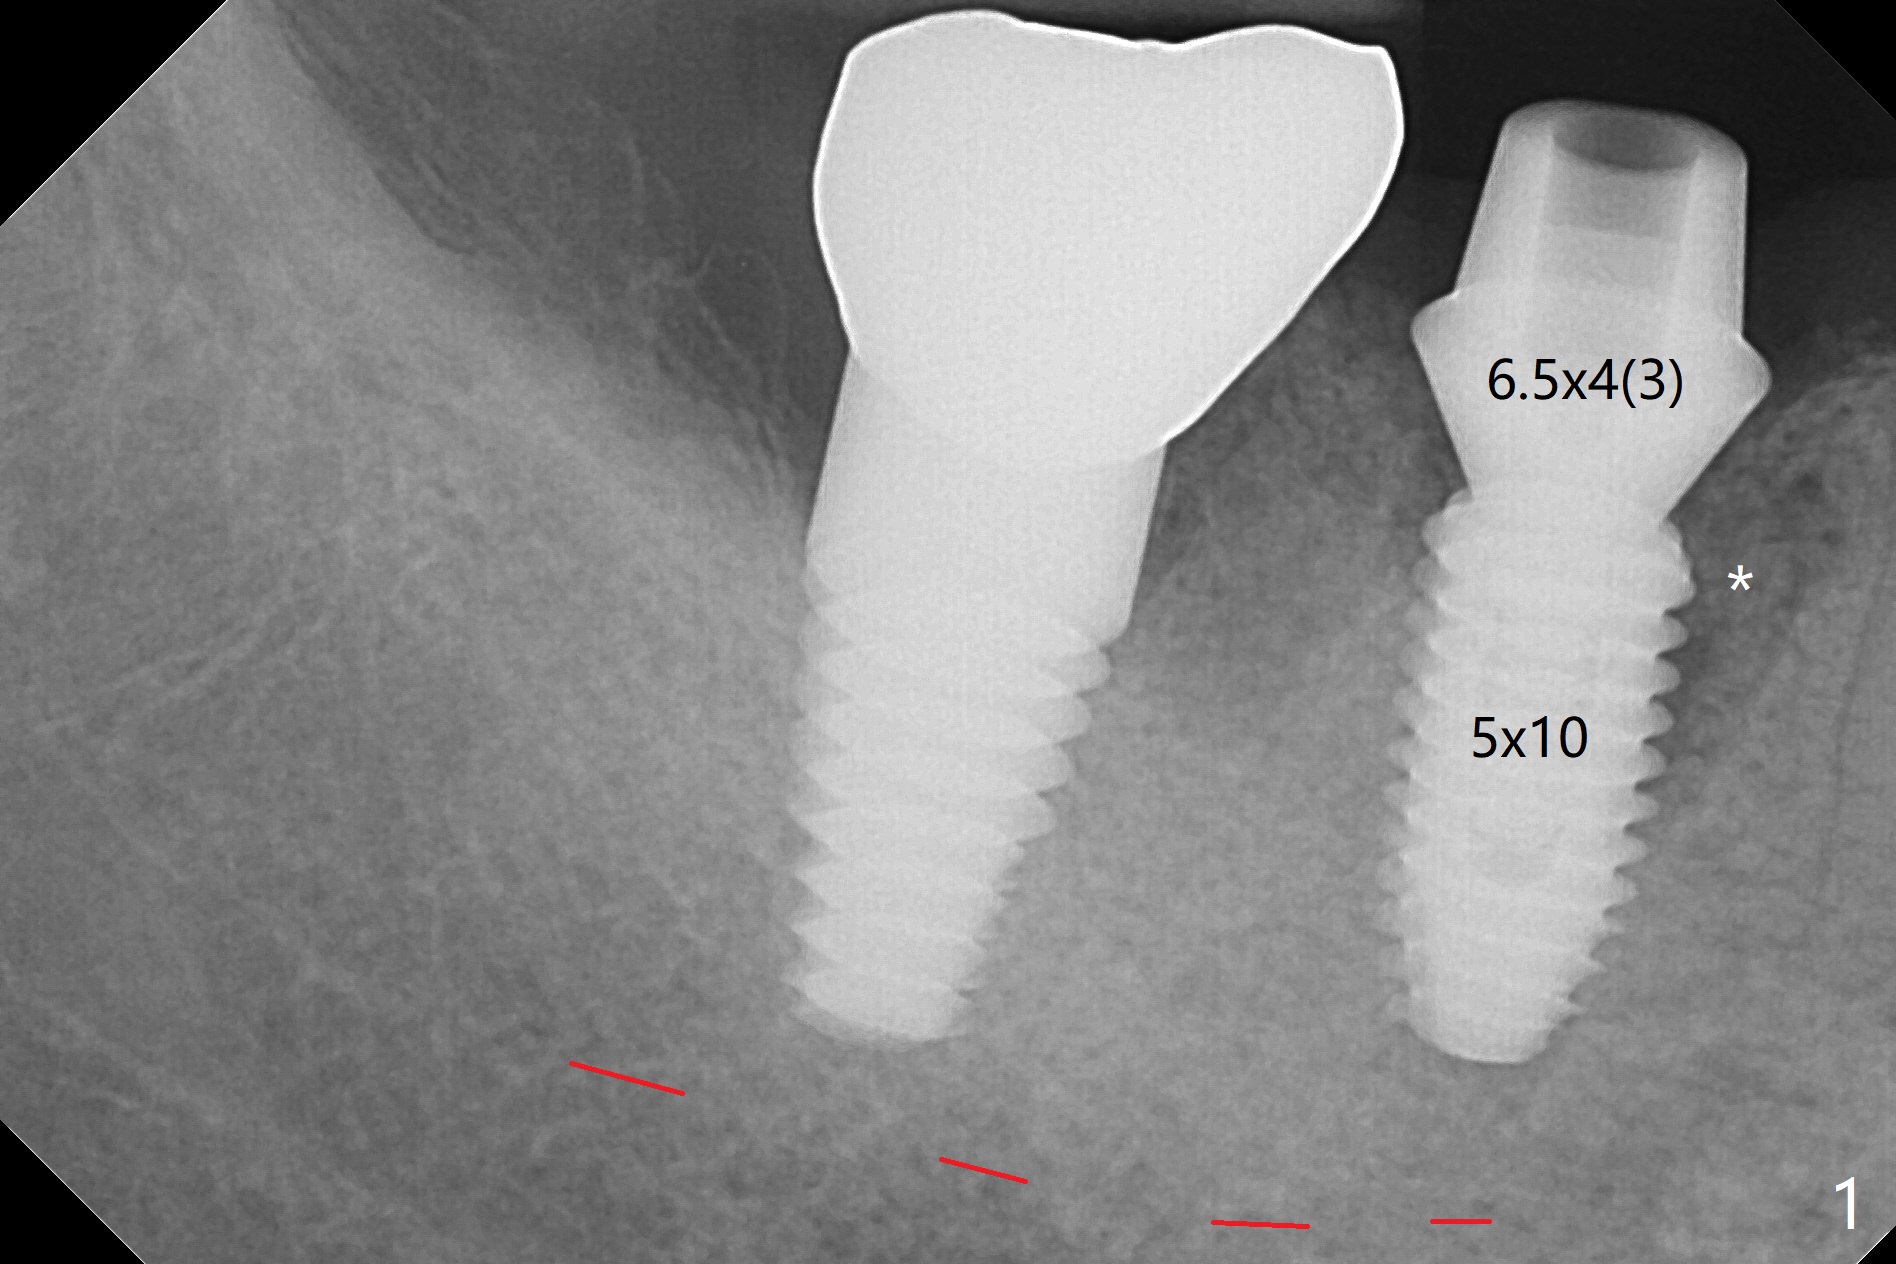

As compared to guided delayed implant placement, the immediate one in the 1st molar needs one more Lidocaine and one Septocaine for pain control. Trajectory is as good as expected with >50 Ncm (Fig.1,2 (red dashed line: superior border of the Inferior Alveolar Canal)). With insertion of Vanilla allograft with autogenous bone (Fig.1 *) and a 6.5x4(3) mm cementation abutment, an immediate provisional (Fig.3 P) is fabricated to keep the graft in place.